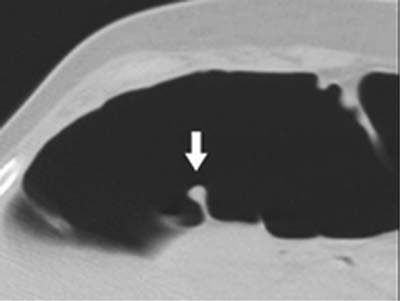

![]() |

| Above, false-positive finding due to a prominent fold. On axial image, the tip of the fold (arrow) appears to be a polyp-like structure, which led to its being incorrectly identified as a polyp. Image courtesy of Dr. Abraham Dachman. |